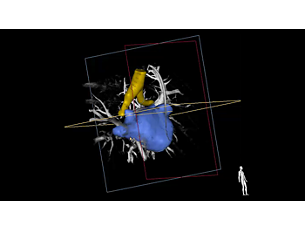

Find similar productsEchoNavigator automatically fuses live 3D TEE and live X-ray in real time. The solution assists heart teams with intuitive image guidance during procedures where both real-time X-ray and echo imaging are used and fused together.

- Improved efficiencies in interventional echo guidance with EchoNavigator live fusion imaging